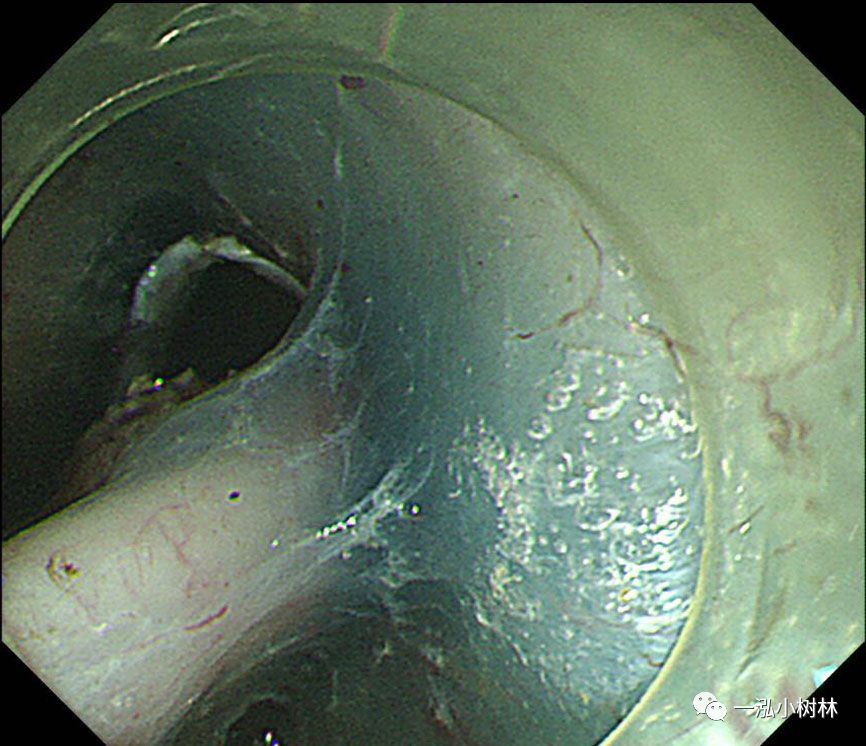

图9 在标本的背面进行钛夹牙线牵引

图10 牵引线从嘴中拉出以产生牵引力